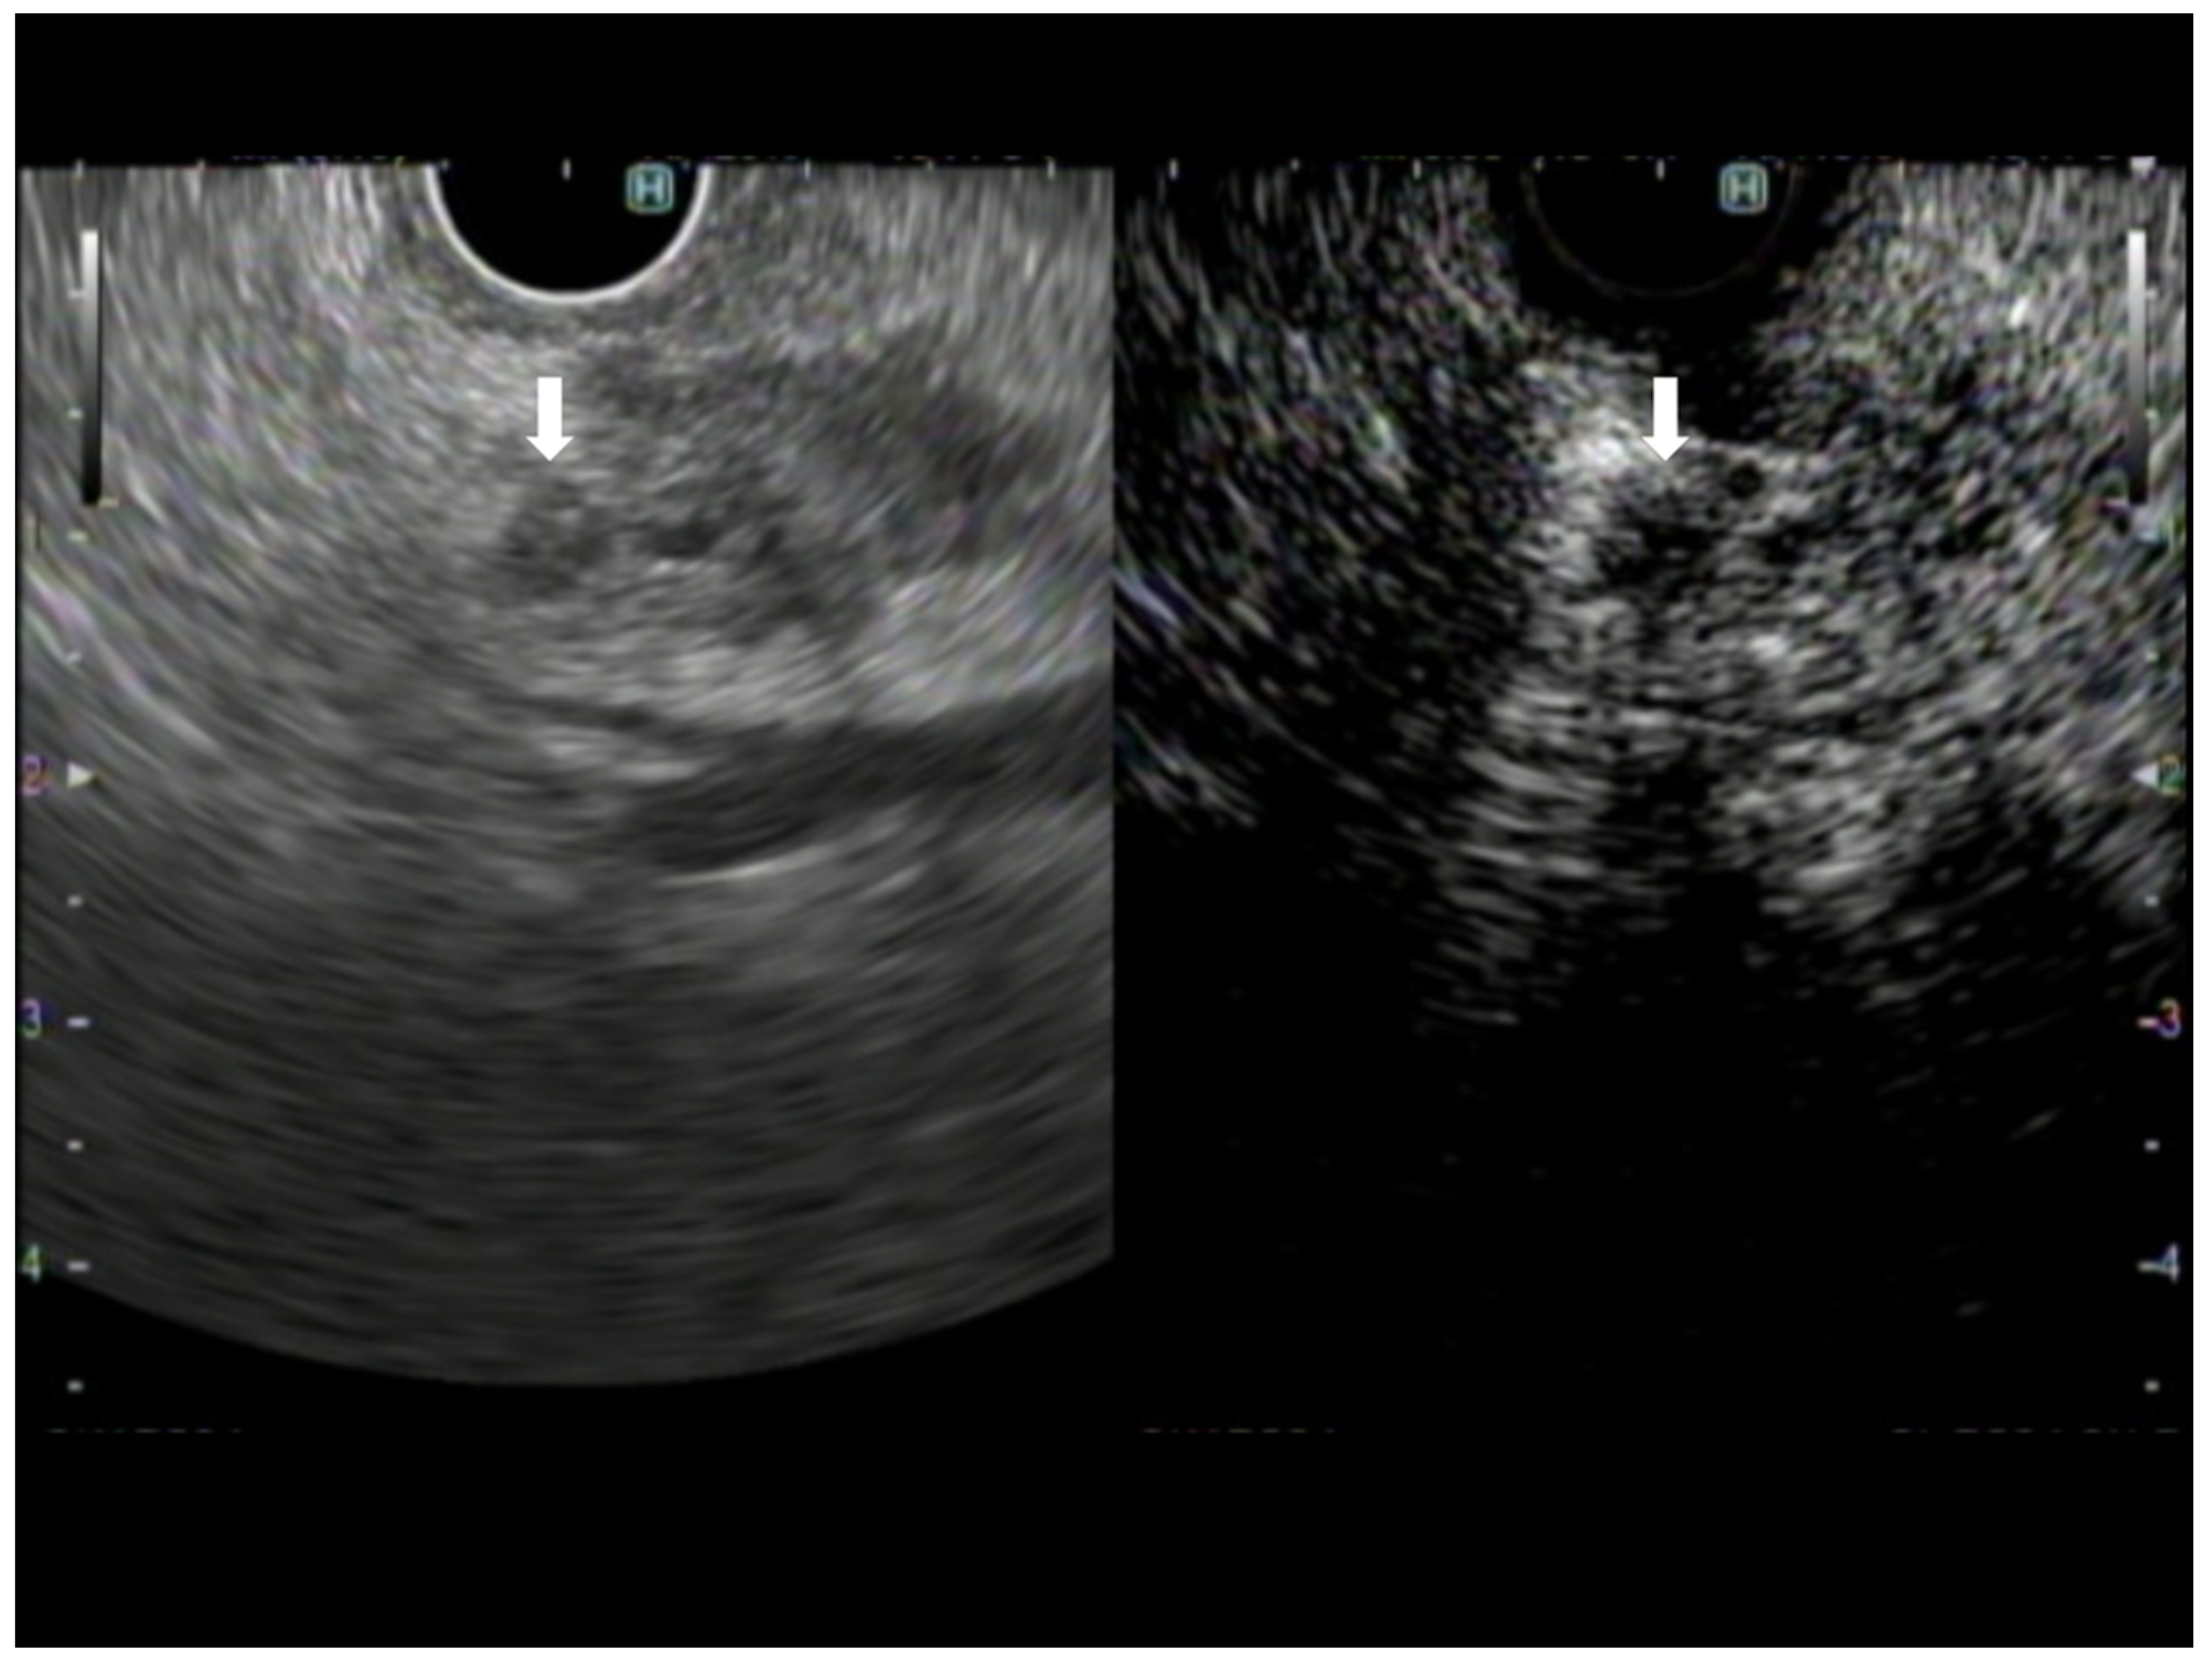

3. Avascular Areas on CH-EUS

- Kamata, K.; Takenaka, M.; Omoto, S.; Miyata, T.; Minaga, K.; Yamao, K.; Imai, H.; Sakurai, T.; Nishida, N.; Chikugo, T.; et al. Impact of avascular areas, as measured by contrast-enhanced harmonic EUS, on the accuracy of FNA for pancreatic adenocarcinoma. Gastrointest. Endosc. 2017, 87, 158–163. [Google Scholar] [CrossRef] [PubMed]